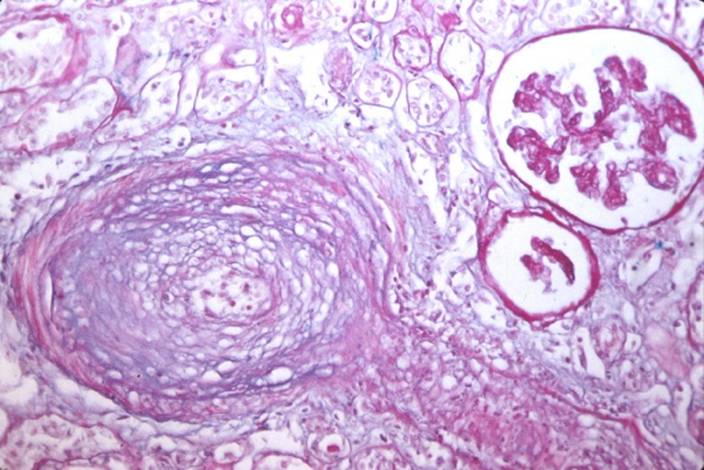

Radiační poškození cévy

Radiační poškození cévy.

Postižení drobných arterií: časné změny jsou mnohem méně vyznačeny, neboť arterie jsou relativně rigidní struktury. Nicméně, v průběhu času se rozvíjí evidentní poškození endotelu a médie. Jde zejména o fragmentaci a porušení membrana elastica interna, degenerativní změny buněk hladké svaloviny médie a její hyalinizace, fibrotizaceadventicie, která přechází do intersticia.

Fibróza arteriální stěny

Fibróza arteriální stěny.